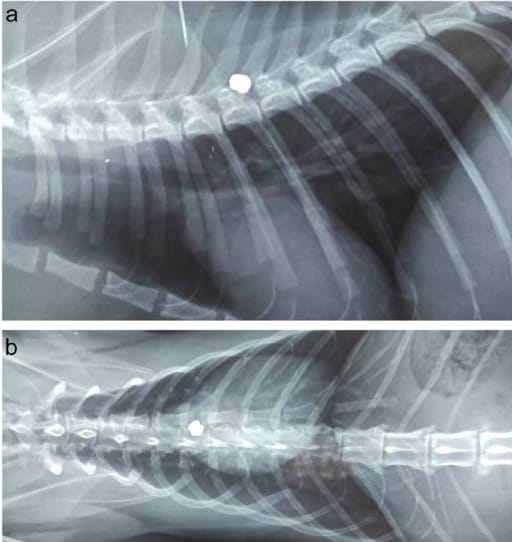

(a) Lateral radiograph showing the lodged airgun projectile (AGP) in the sixth thoracic vertebrae (patient 4); (b) dorsoventral radiograph showing the lodged AGP in the sixth thoracic vertebrae (patient 4)

Medical records from 1998 to 2022 were reviewed for cats with neurological deficits linked to lodged 4.5 mm airgun projectiles in the spinal canal. Cats were classified by injury location (cervical, thoracolumbar, lumbosacral), severity of neurological signs, treatment approach (surgical vs. conservative), and season of presentation. Radiographic imaging confirmed projectile presence, and follow-ups assessed neurological recovery, mobility, and bladder function.